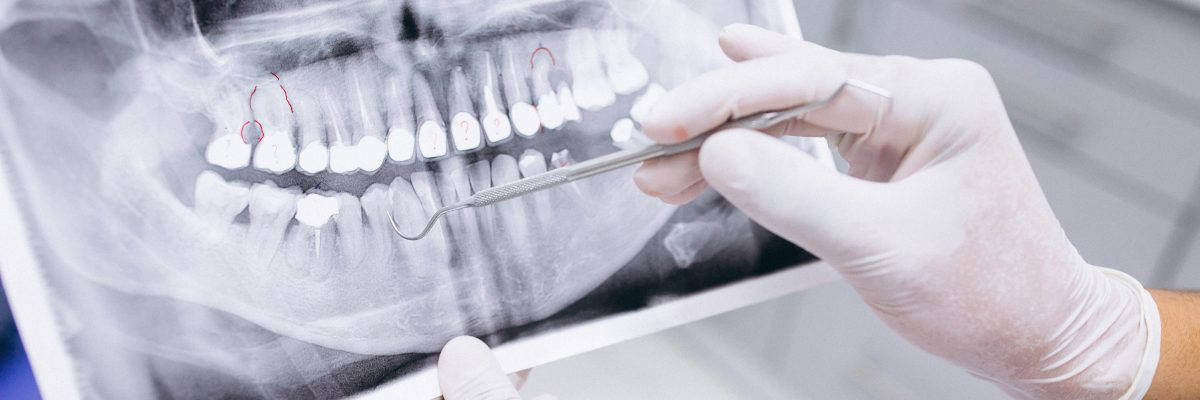

Radiografia periapical

Radiografia periapical de diagnóstico.